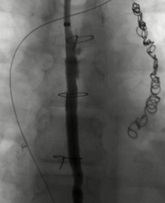

塑型支气管炎胸导管支架技术细节 Thoracic duct stenting

淋巴结造影和明确胸导管入路后,经贵要静脉穿刺,经血管桥0.018导丝,引导血管内抓捕器到静脉角 |

血管内抓捕器抓住胸导管内进入静脉的0.018导丝,建立through to through的通路,6Fr鞘进入胸导管,直径5mm Viabahn 覆膜支架释放,并用5mm直径的球囊扩张 |

术后造影剂注射显示胸导管淋巴流正常。 |